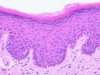

What is shown by letters a-e in this picture?

a - stratum basale

b - stratum spinosum

c - stratum granulosum

d - stratum lucidum

e - stratum corneum